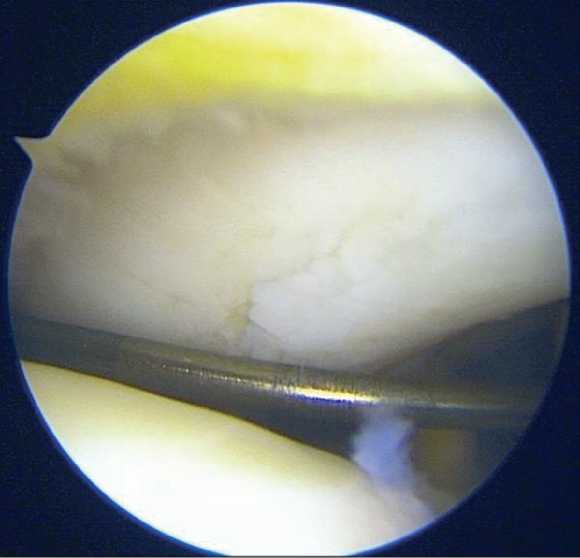

Рисунок 8. Снимок до обработки поверхности дефекта хрящевой ткани медиального мыщелка, который заполнен фиброзоподобной тканью

Через пять недель после первичной артроскопии правого коленного сустава пациент был приглашён для проведения повторного артроскопического вмешательства с целью имплантации биомедицинского клеточного продукта аутологичных хондроцитов в область хрящевого дефекта медиального мыщелка бедренной кости. Новых визуальных изменений по сравнению с данными первой артроскопии выявлено не было. После ревизии структур коленного сустава выполнили обработку дефекта до уровня субхондральной кости, затем осуществлена имплантация клеточного продукта в соответствии с ранее описанной методикой (Рисунок 9).

Рисунок 9. Аутологичные хондросферы распределены на поверхности дефекта хряща медиального мыщелка бедренной кости